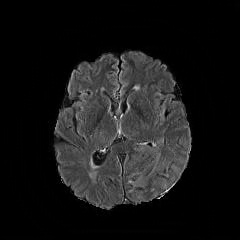

We observe that the generated normal-looking from ANT-GAN can also be used to directly segment the image, since the only difference between a synthesized normal-looking image and its real abnormal counterpart is region with the lesion. To illustrate this, we calculate the absolute difference between x𝑥x and 𝒢A2N(x)subscript𝒢A2N𝑥\mathcal{G}_{\rm{A2N}}(x) and show the segmentation after binary thresholding at 0.1 in Figure 9.

(a) Tumor x𝑥x

(b) 𝒢A2N(x)subscript𝒢A2N𝑥\mathcal{G}_{\rm{A2N}}(x)

(c) Prediction

(d) Label

Figure 9: Example segmentation obtained by taking the absolute difference between the real tumor MRI x𝑥x and the generated normal-looking MRI 𝒢A2N(x)subscript𝒢A2N𝑥\mathcal{G}_{\rm{A2N}}(x), after binarization at a preset threshold.